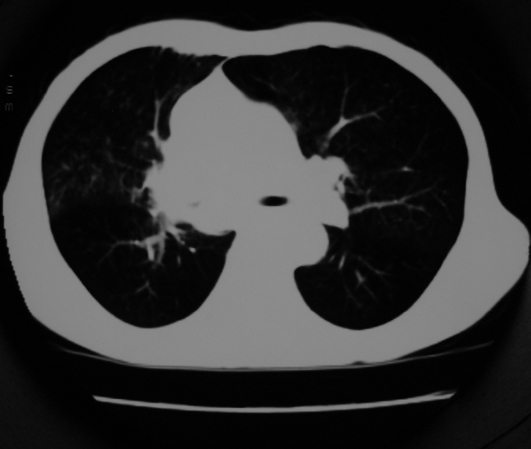

以下是引用同在2007-1-27 14:13:00的发言:[br]支持右侧中央型肺癌伴阻塞性病变.

以下是引用zjzjr在2007-1-27 16:56:00的发言:[br]支持右肺中心型肺癌伴阻塞性肺炎.